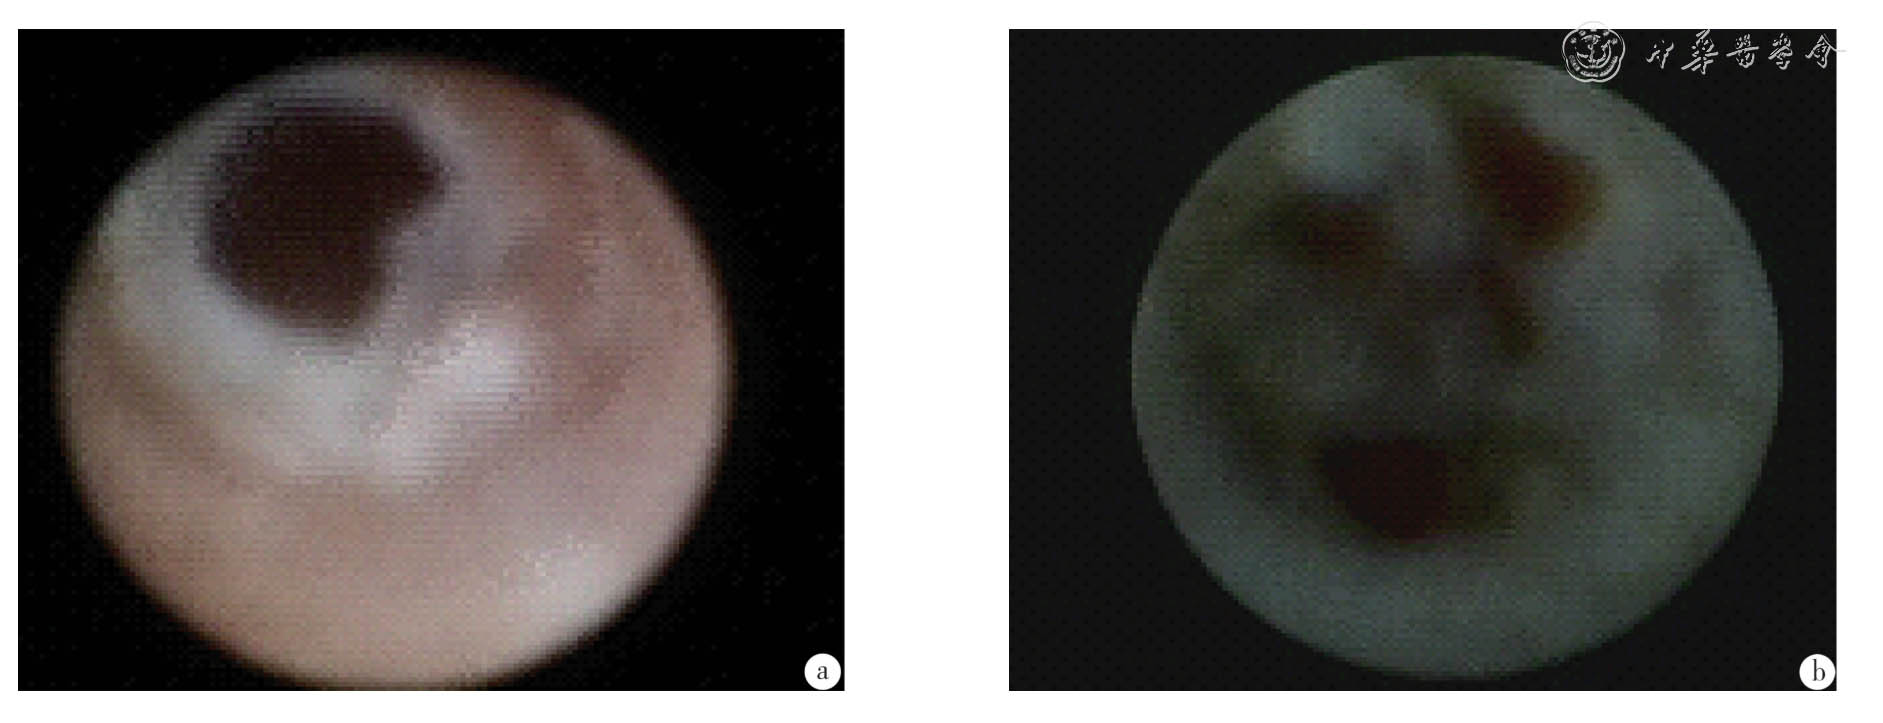

本研究5 级图像特征(图6)包括:病变为多发、位于3 级及以下乳管或末梢、不规则、无蒂,沿管壁纵行扩展亦可沿管壁环行生长、灰白色或多彩,管壁粗糙、增厚、僵硬、弹性差或管壁表面有广泛的出血斑,可合并末梢出血[8],恶性率为81.3%(78/96)。Rose 等[5,9]描述导管内癌(DCIS)的纤维乳管镜下表现:管腔内弥漫性不规则增生及管壁粗糙,指出这是区分DCIS 和乳头状瘤的特征性表现,也指出管壁粗糙和管腔出血应考虑恶性。

图6 乳腺导管镜分级5 级

a:管壁粗糙、增厚、僵硬,表面有广泛的出血斑;b:病变浅表,不规则、无蒂,多彩